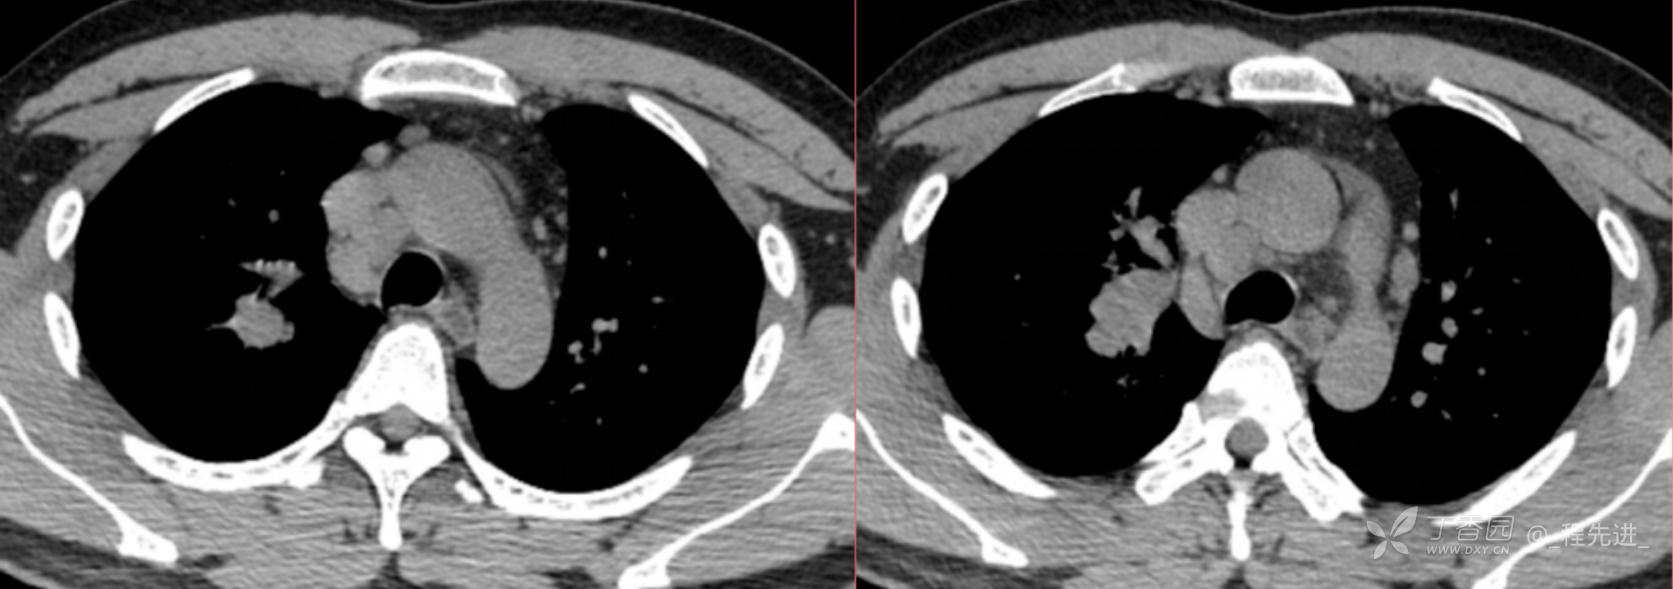

1月特别精彩病例|阵发性刺激性咳嗽,咳少量白色粘液痰1周,期待你的挑战【结果公布】

患者年龄:34岁

简要病史:患者一周前无明显诱因出现阵发性刺激性咳嗽,咳少量白色粘液痰,咳嗽无明显昼夜节律性,无发热、畏冷、寒战,无头痛、胸闷、胸痛,自行服药后 (具体不详) 症状无缓解,3天前当地医院胸片检查示右上病变

辅助检查:肺肿瘤标志物: 神经元特异性烯醇化酶(NSE): 35.72ng/ml(参考值0-16.3);非小细胞肺癌相关抗原211、癌胚抗原、糖类抗原125、铁蛋白、鳞状细胞癌抗原未见异常